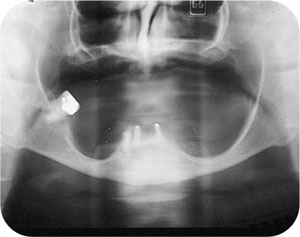

The anatomical changes which occur following extraction of natural teeth can broadly be divided into intraoral and extraoral changes. These will differ between individuals who remain partially dentate and those who are edentulous following tooth loss. As people age, loss of alveolar bone is inevitable. However, following total tooth loss, alveolar bone resorption is greatly increased. Alveolar bone height and width decrease markedly (Figs. 1-1 and 1-2). Most of this change occurs in the first year following extractions, but remains an inexorable process throughout life. Resorption occurs on the buccal aspect of the maxillary ridge and the lingual aspect of the mandibular ridge. In a mixed longitudinal study over 25 years, Tallgren demonstrated the extent of bone loss in edentulous individuals. She demonstrated that the loss of bone is four times greater in the mandible than the maxilla. Despite extensive research, the reason for great individual variation in bone loss remains unclear. It seems likely that a combination of local and systemic factors may be responsible for this phenomenon.

Fig 1-2 Orthopantomogram of 75-year-old female with retained dental roots in the anterior mandible. Note the bone height around teeth compared to edentate areas in the lower jaw.